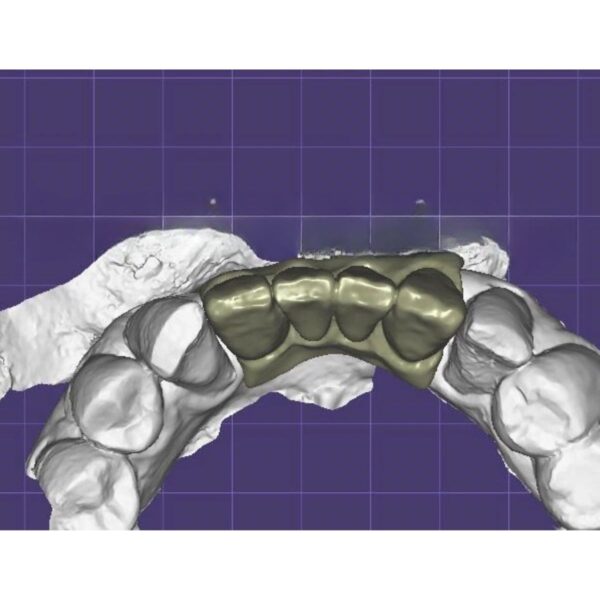

China Dental Design Complex Case Gallery

Challenging Projects That Showcase Our China Dental Design Expertise

Dental Crown Design

- Aesthetic zone reconstructions

- Complex occlusal cases